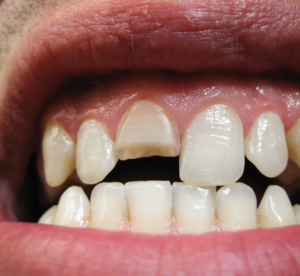

Imagem de um sorriso exibindo um dente frontal quebrado. A cena ilustra problemas odontológicos como fraturas dentárias, desgaste ou traumas bucais. Isso são possíveis causas da procura pelo sistema dentista 24 horas ou consultas de agendamento.

Fraturas dentais podem se manifestar através de dor intensa, sensibilidade ao frio ou calor e dificuldade para mastigar. Ao notar qualquer um desses sintomas, o paciente deve procurar um profissional. O atendimento rápido não só alivia a dor como também pode salvar o dente afetado.

Imagem de um sorriso feminino com um dente incisivo quebrado. A cena destaca problemas odontológicos, como fraturas dentárias, que podem exigir tratamento estético ou restaurador, ilustrando possíveis causas da procura pelo sistema dentista 24 horas ou consulta de agendamento.